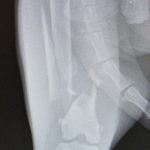

'זילולה' נעלמה ליותר משבוע וחזרה כשהיא לא דורכת על רגלה האחורית. בבדיקה וצילום במרפאה התגלה ש'זילולה' כנראה נדרסה ושברה שבר נוראי את רגלה. היא כנראה שברה את רגלה ביום שנעלמה, מאחר והשבר כבר לא היה "טרי", מה שסיבך מאוד את הטיפול בה. ואם לא די בכך, התקציב הטיפולי של 'זילולה' היה מוגבל ולא איפשר תיקון אורטופדי מתקדם.

כדי להציל את הרגל שלה, ביצענו ניתוח אורטופדי הרואי ומורכב, בו הצלחנו להחזיר את העצמות למנח כמעט אנטומי. וזאת כנגד כל הסיכויים כי השבר כבר התחיל בתהליך איחוי.